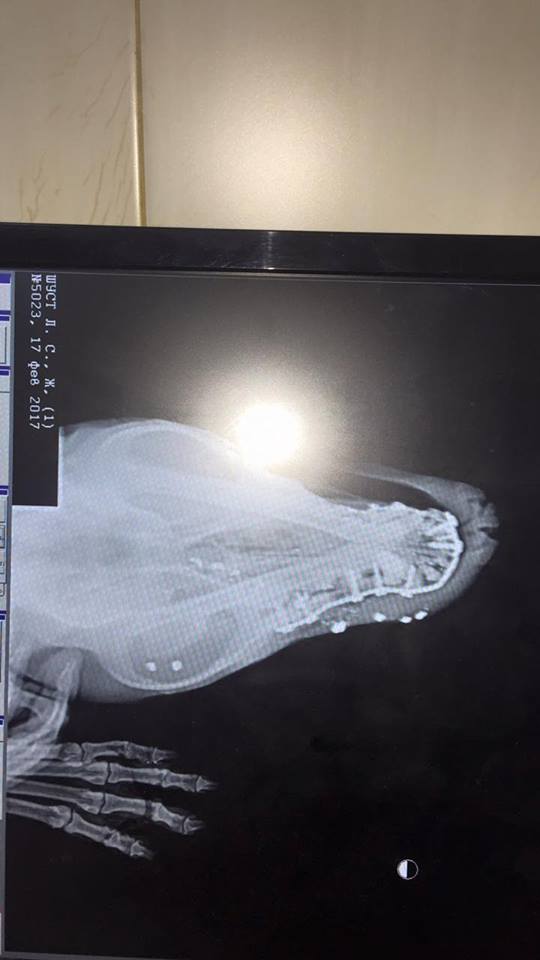

— После осмотра и рентгена – 10 пулевых отверстий. Это что, вместо мишени? Простреленный, пневмоторакс, подшили плевральный дренаж, постоянно откачивается воздух. Пока никаких прогнозов, - сказано в сообщении.